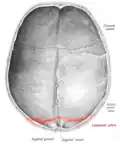

|  Lambdoid suture (labeled at bottom right) | |

Lambdoid suture seen from above. Lambdoid suture seen from above.

Lambdoid suture seen from inside. Lambdoid suture seen from inside.